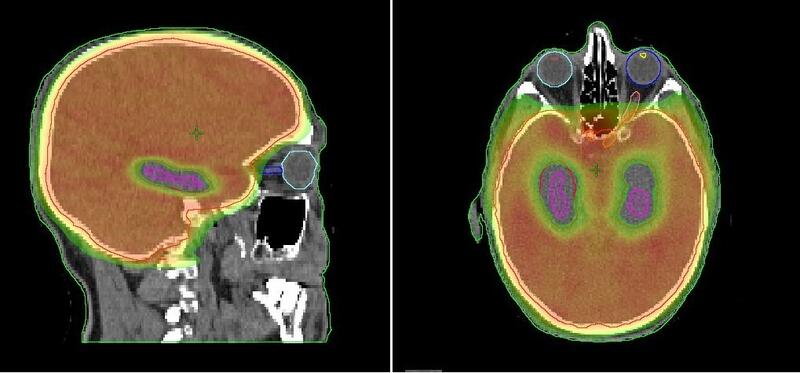

Con la protección del hipocampo, una pequeña zona situada en la región central del cerebro vinculada, entre otras cosas, a la memoria y al aprendizaje, permite reducir "hasta cinco veces" la afectación sobre la memoria en los pacientes estudiados.

De hecho, en los 150 casos analizados, aquellos en los cuales se protegió esta área tenían una afectación de menos de un 6% en la memoria después de recibir el tratamiento, comparada con cerca del 24% en aquellos que se sometieron al abordaje convencional.